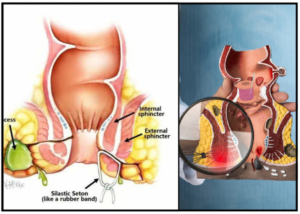

Read MorePiles fissure fistula surgery

Laser surgery is an increasingly popular treatment for various anorectal...